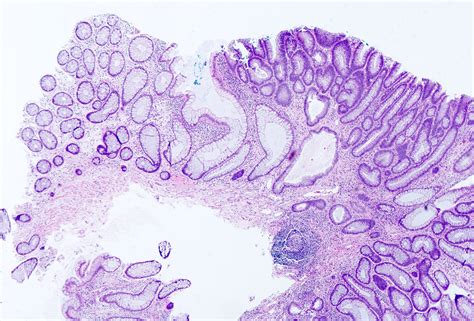

A tubular adenoma is a type of polyp that forms on the inner lining of the colon. These polyps are composed of glandular tissue and are characterized by their tubular shape. Tubular adenomas are the most common type of adenomatous polyps, which are known to have the potential to become malignant if left untreated. Early detection and removal of these polyps are essential for preventing the development of colorectal cancer.